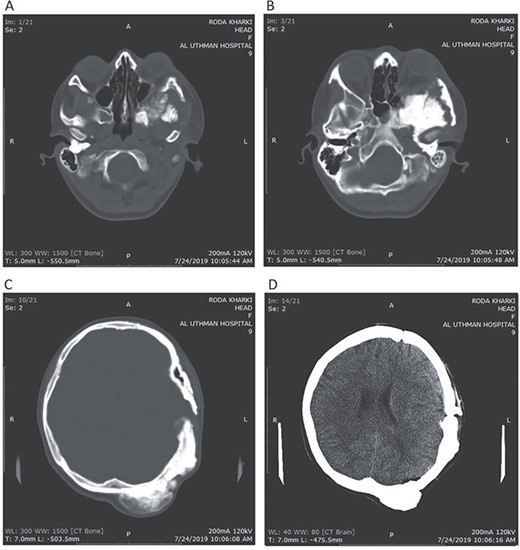

Postoperative CT head bone window (A–C). A. Regression of the pressure on the maxillary sinus. B. Decline of the exophthalmos. C. The parietal bone after excision of the masses. Tissue window (D). Regression of the pressure on left lateral ventricle and decline of the midline shift.

A 17-year-old female presented with a history of osteosarcoma that was confirmed after undergoing a surgery to remove an enlarging bone tumor in the left temporal region 2 years ago. She later got pregnant and delivered her child but never got back for a checkup until she was admitted to our hospital with a severe and unresponsive to medication headache that progressed over the course of 6 months and blurred vision that progressed to complete left-sided vision loss. Physical examination revealed a tough and mobile yet fixed at the base 7-cm mass towards the left of the frontal bone. Many more masses were revealed in the left side of the skull including the anterior cranial fossa, orbit, base of the skull and the left part of the occipital region where the previous procedure was performed (Fig. 1). These masses had been increasing in size probably under the influence of pregnancy hormones causing pain that radiated along the orbital and maxillary branches of the left trigeminal nerve. Physical examination and past medical history were otherwise unremarkable. Laboratory tests were all normal, and her family history was negative. Staging studies showed no evidence of distant metastatic disease in the chest, the abdomen and the pelvis. CT scan of the skull revealed a bone-forming non-lytic lesion accompanied by periosteal reaction. This lesion bulges to the outside towards the scalp spreading into both the soft tissues and the inside of the entire left side of the skull with a sunburst-pattern (Figs 2 and 3). Its rims are unsymmetrical and pointy, and it bulges into the left orbit outside the muscles causing exophthalmos with a semi-complete proptosis of the eyeball out of the orbit (Figs 2 and 3). This lesion applies pressure to the left frontal and temporal lobes causing mild edema in both these lobes without invading the brain tissue. This edema in turn applies pressure to the left lateral ventricles (minor shift of the elements of the midline to the right side can be seen on CT) (Fig. 4). Due to the tumor’s wide spread, the surgical procedure was performed in two stages (approximately 6-hour-long each). In the first stage, the bone mass was removed through a procedure of wide skull approach including the frontal, temporal and parietal bones and a removal of the invading part of the temporal muscle. Moreover, the lateral wall and roof of the left orbit were removed, the left optic nerve was dissected free and part of the meninges was removed and replaced with an autogenic patch from the fascia lata. Then, the bone loss was compensated for by using bone cement Synicem VTP (poly methyl methacrylate and Barium sulfate), and the orbit was rebuilt; the eyeball was placed back with noticeable decline of the exophthalmos. In the second stage, a complementary left parietal occipital incision of the previous approach was performed 3 weeks later; the remaining of the frontal and occipital bones was removed, and a partial mastoid surgery was done. Furthermore, the cavernous sinus were revealed and found to be not invaded. Later on, the normal skull shape was restored using the same cement. The histopathology of the lesion revealed proliferation of neoplastic chondroblasts, osteoblasts and spindle-shaped cells. The features are consistent with low-grade chondroblastic osteosarcoma (Fig. 5). The patient did not need ICU admission. She recovered well 3 days after the surgery and was discharged with no deficits. A CT scan that was performed post-operatively revealed that the masses were successfully excised (Figs 6 and 7). At the last follow-up 1 month post-operation, the patient was scheduled to undergo a course of radiotherapy, 60 Gy of radiotherapy in 30 fractions over 4 weeks without chemotherapy, as it is not recommended with low-grade osteosarcoma.